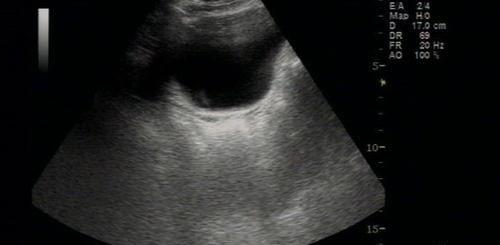

人们总有一些错误的认知,觉得先天性无子宫的女性会衰老快,后期做子宫切除手术的也会活的不久,更是有传闻说“摘除子宫最多活十年”,那么事实究竟是怎么样的呢?

先天性无子宫并不会衰老快,所谓的“摘除子宫最多活十年”也仅仅是谣言,因为子宫主要是孕育胎儿以及排出月经,所以对于身体来说,切除了子宫,主要是剥夺了女性生育的权利,并没有多大影响。

切除子宫之后女性没有孕育胎儿的器官,则不能正常的怀孕; 不能有月经来潮,因为月经的发生是子宫内膜受卵巢激素周期性改变的影响; 容易发生盆底功能障碍性疾病,子宫是女性盆底重要的脏器,起到支撑的作用; 切除子宫的女性可能会影响卵巢的功能,过早的出现围绝经期综合征的一系列表现。一般维持女性正常激素水平,主要是在于卵巢,所以这个阶段卵巢功能只要正常,一般就可以正常的存活,但如果是因为某些恶性病变切除了子宫,大多说明病人的生存时间是有限的,这才会影响到女性的寿命。

所谓的“摘除子宫最多活十年”并不科学,要知道无论是先天性无子宫还是单纯摘除子宫一般不会影响寿命,但如果是因为女性子宫有病变以后做了子宫摘除术,这时可能会对女性又影响。

假如患有子宫内膜癌做手术把子宫摘除了,经复查后又出现了转移,这种情况下如果出现恶液质且消耗很厉害,各个脏器都有累及,患者存活10年也较难。

先天性无子宫属于生殖器先天缺如的一种情况并不影响人的寿命,但如果是因为后天疾病导致的子宫切除术,如子宫内膜癌、宫颈癌等,能活多久就要看疾病的严重程度、分期了。